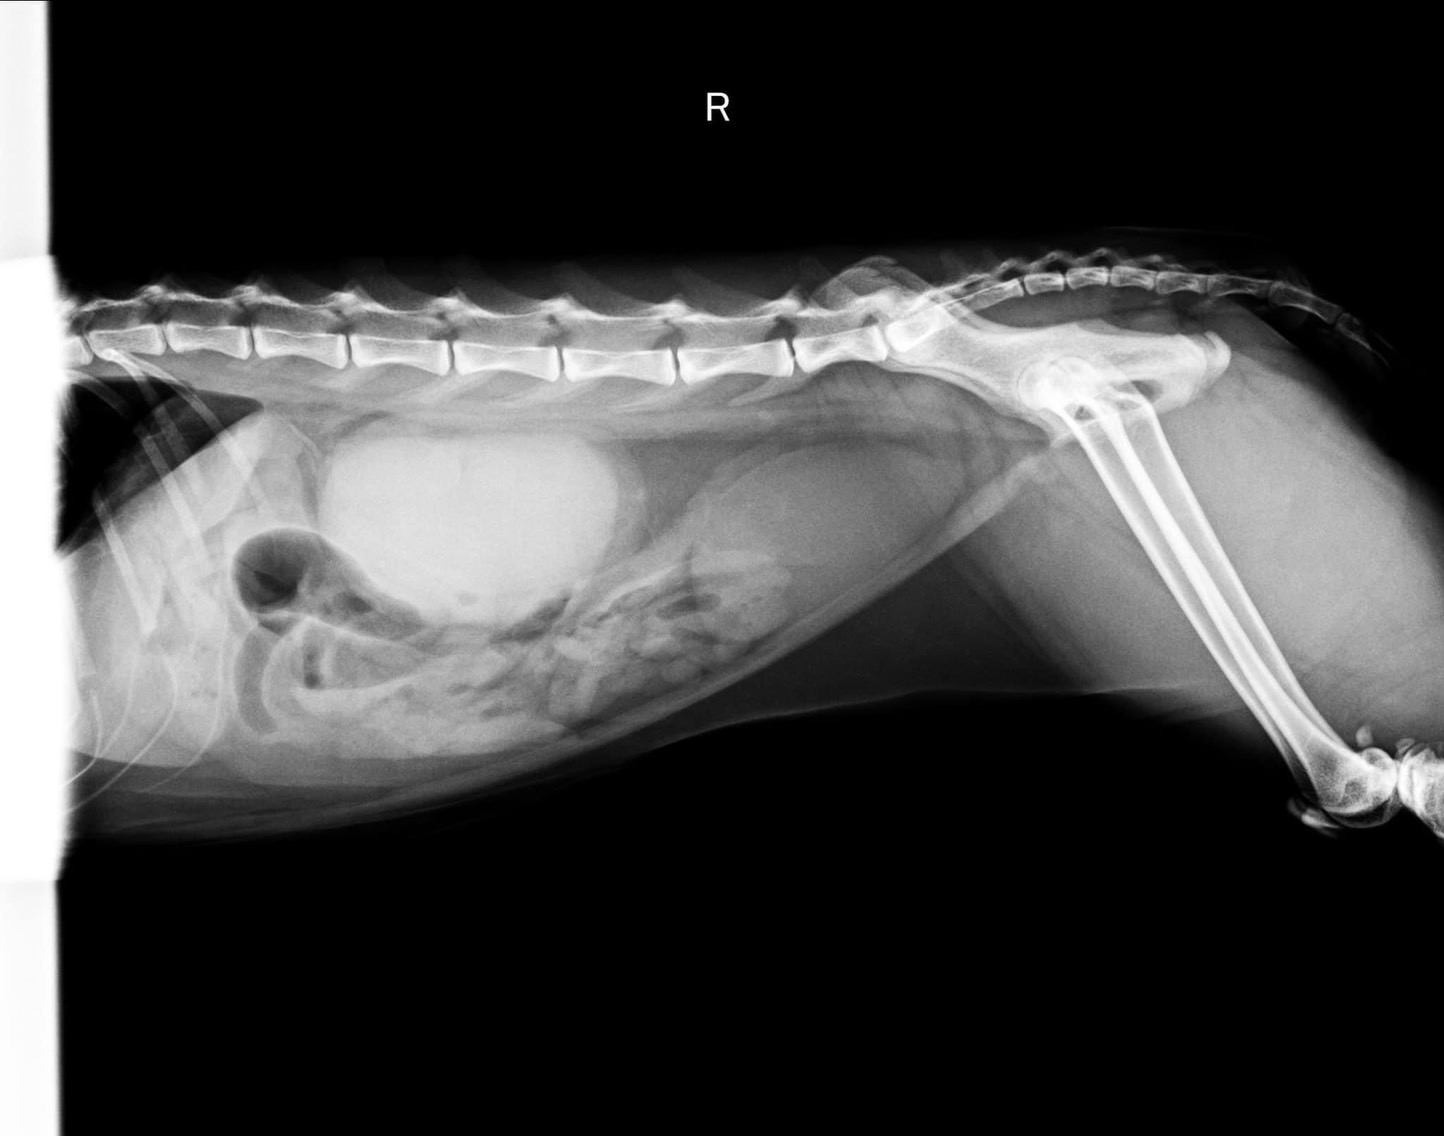

理學檢查發現小花血色蒼白,口腔牙齦嚴重發炎,靠近喉頭位置扁桃腺又紅又腫,腹腔超音波及腹腔x光影像皆發現雙腎不規則腫大。